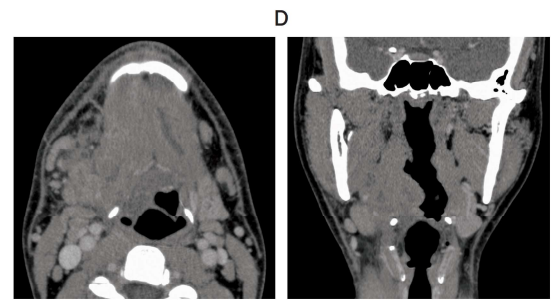

80 歳の女性。上顎右側歯肉の腫脹を主訴として来院した。 2 か月前から徐々に増大してきたという。15 年前に脳梗塞を発症し、10 年前から関節リウマチと骨粗鬆症で投薬を受けている。初診時の口腔内写真(別冊No. 7A)、エックス線画像(別冊No. 7B)、造影 CT(別冊No. 7C)、FDG-PET/CT(別冊No. 7D)及び生検時のH-E 染色病理組織像(別冊No. 7E)を別に示す。

病変の誘因と考えられるのはどれか。 1 つ選べ。

解答:b

解説:

関節リウマチの薬といえば、メトトレキサート。

メトトレキサートの長期投与により、メトトレキサート関連リンパ増殖性疾患が引き起こされる。

Eの病理組織像を見ると、リンパ球の増殖、異型リンパ球がみられる。